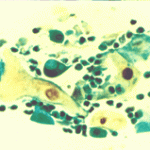

Περιστατικό ασθενούς που παρακολουθείται στο ιατρείο μας από το 1993, τότε ηλικίας 37 ετών, αρχικά λόγω ασυμπατωματικού κυτταρολογικά εμμένοντας έρπητος τραχήλου της μήτρας. Το γεγονός αυτό μας οδήγησε στην διερεύνηση της περιπτώσεως. Η ασθενής επασχε από A.I.D.S.

Είχαμε την ευκαρία να παρακολουθήσουμε ανά 6μηνο γυναικολογικά, κολποσκοιπικά και κυτταρολογικά την γυναίκα από το 1993 μεχρι και το 2008. Από τις εξετασεις αυτές, παρουσιάζουμε χαρακτηριστικές κυτταρολογικές εικόνες . Όι παρακάτω κυτταρολογικές εικονες προέρχονται από την 2η κατά σειρά εξέταση της ασθενούς το 1993. Οι κυτταρολογικές αλλοιώσεις ερπητος συνεχίζουν να υφίστανται.

Ταση γιγαντιοκυττάρωσης όλων των επιθηλιακώ στοιβάδων, κοιλοκυττάρωση, διογκωμένοι υπερχρωματικοί και ανισομεγέθεις πυρήνες , με διάλυση δομής χρωματίνης, συχνά διογκωμενοι πυρήνες με εικόνα φαινομένου ΄΄θολού γυαλιού΄΄